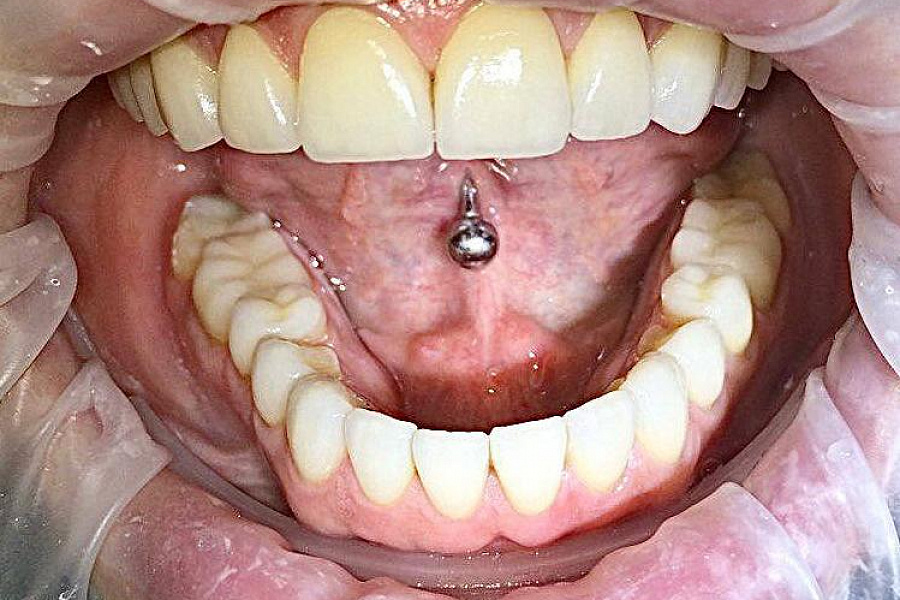

Провели санацию, сделали и установили красивые натуральные виниры.

Что получили?

Результат на фото говорит лучше всяких слов. Пациентка очень довольна результатом!

Результат лечения